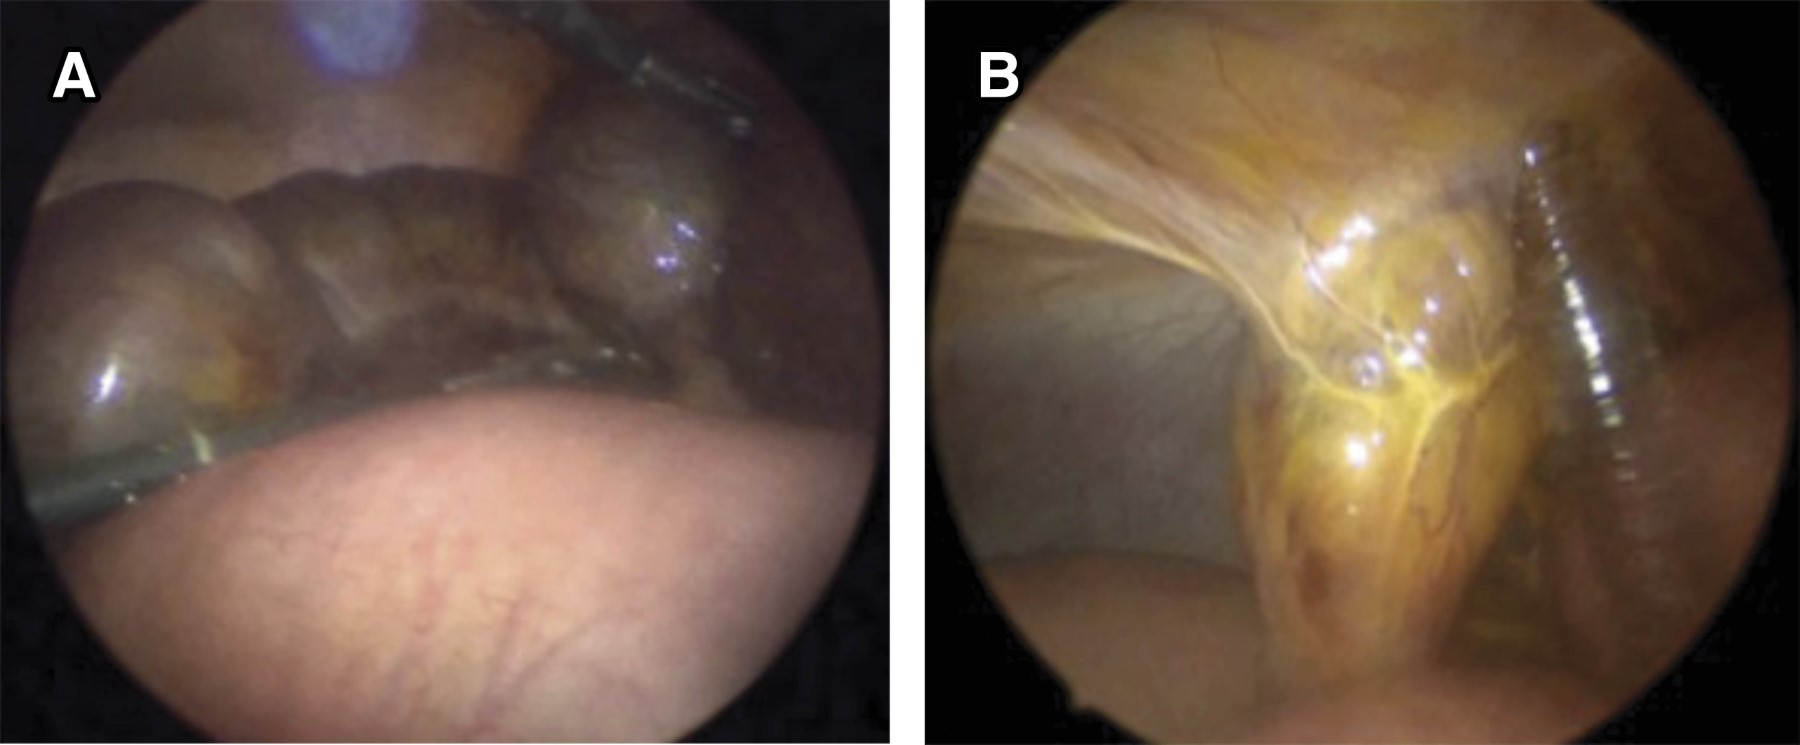

Figure 1